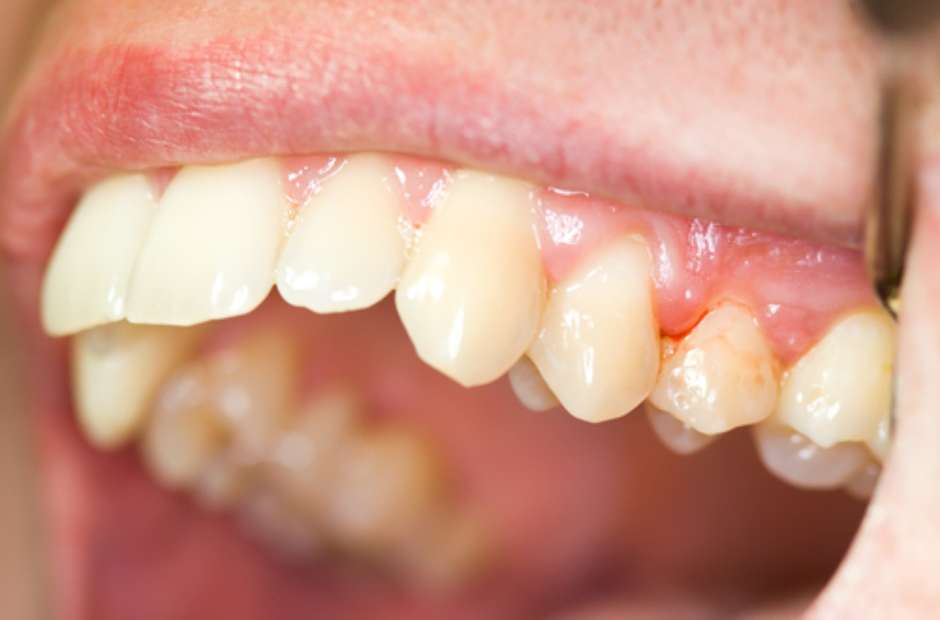

Vamos falar sério agora sobre periodontite agressiva juvenil. Se você ou alguém que você conhece está lidando com isso, sabe que é um assunto delicado. Basicamente, quando a doença periodontal avança e a inflamação já causou perdas ósseas significativas, a cirurgia pode ser o caminho. É aquela situação em que a limpeza profunda que fazemos não consegue mais alcançar as bactérias mais problemáticas.

Eu já vi casos onde a gengiva se retrai muito, deixando a raiz do dente exposta. Isso não é só questão estética, viu? Aumenta a sensibilidade e o risco de cáries nessa área. A cirurgia periodontal entra para tentar recuperar o suporte dos dentes, removendo as bolsas periodontais e, em alguns casos, até regenerando o osso perdido. É um procedimento para quando outras abordagens não foram suficientes, entende?

O objetivo principal da cirurgia é tornar a área mais fácil de limpar, removendo as bactérias que se escondem nas bolsas profundas. Isso ajuda a parar a progressão da doença e a salvar os dentes. É um passo importante para quem busca um tratamento mais completo contra a periodontite agressiva juvenil, pensando na saúde bucal a longo prazo.

Gengivas que sangram facilmente, inchaço e vermelhidão são os primeiros alertas. Mau hálito persistente também pode indicar algo. Observe o sorriso do seu filho atentamente.